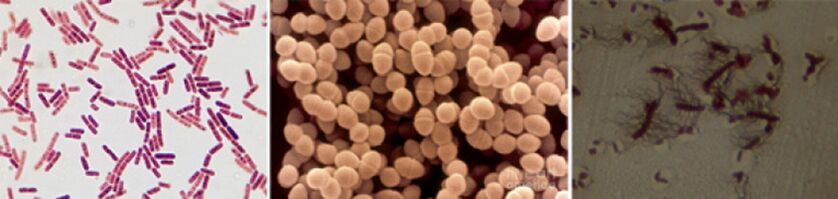

Parmi les agents responsables de la prostatite chronique figurent les agents pathogènes suivants :

- Dans 90 % des cas, la maladie révèle des bactéries à Gram négatif telles que Escherichia coli (Escherichia coli), Enterococcus faecalis (entérocoque fécal) et, moins fréquemment, Pseudomonas aeruginosa, Klebsiella spp., Proteus spp., Pseudomonas aeruginosa, Enterobacter aerogenes et Acinetobacter. spp. Les bactéries à Gram positif, les entérorocoques, les streptocoques et les staphylocoques sont rares.

- Le rôle des staphylocoques à coagulase négative, des ureaplasma, des chlamydia, des trichomonas, des gardnerella, des bactéries anaérobies et des champignons du genre Candida n'a pas été entièrement élucidé.